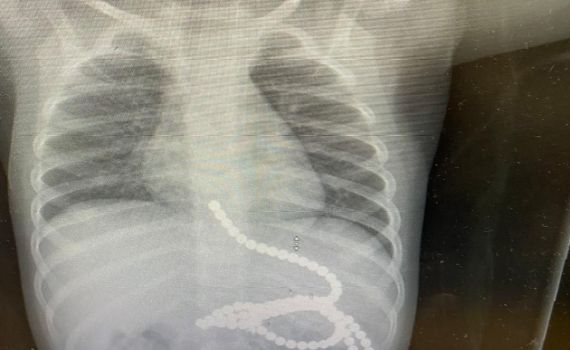

עם הגעתו, בוצע צילום רנטגן, בו נראתה כמות גדולה של מגנטים בקיבה ובאזור הוושט. בעקבות זאת עבר הפעוט אנדוסקופיה, במהלכה נשלפו מרבית המגנטים מגופו. הפעולה בוצעה ע"י ד"ר אורית אלקיים, גסטרו-אנטרולוגית ילדים ורופאה בכירה באגף ילדים, בשיתוף עם צוות גסטרו-אנטרולוגיה מבוגרים שבהובלת ד"ר ויסאם סבית וד"ר אמיר שאהין.